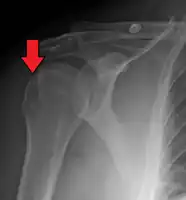

| Anterior shoulder dislocation on X-ray with a large Hill–Sachs lesion | |

A Hill–Sachs lesion, or Hill–Sachs fracture, is a cortical depression in the posterolateral head of the humerus. It results from forceful impaction of the humeral head against the anteroinferior glenoid rim when the shoulder is dislocated anteriorly.

Diagnosis can be suspected by history and physical examination which is usually followed by imaging. Because of the mechanism of injury, apprehension of anterior dislocation is common with provocative maneuvers. Hill–Sachs lesions have been classified as "engaging" or "non-engaging", with engaging lesions defined by the ability of the glenoid to sublux into the humeral head defect during abduction and external rotation. Engaging dislocations have a higher risk of recurrent anterior dislocation, and their presence can help guide surgical management.[2] Imaging diagnosis conventionally begins with plain film radiography. Generally, anteroposterior (AP) radiographs of the shoulder with the arm in internal rotation offer the best yield while axillary views and AP radiographs with external rotation tend to obscure the defect. However, pain and tenderness in the injured joint make appropriate positioning difficult and in a recent study of plain film x-ray for Hill–Sachs lesions, the sensitivity was only about 20%. i.e. the finding was not visible on plain film x-ray about 80% of the time.[3]

X-ray at left shows anterior dislocation in a young man after trying to get up from his bed. X-ray at right shows same shoulder after reduction and internal rotation, revealing both a Bankart lesion and a Hill-Sachs lesion.